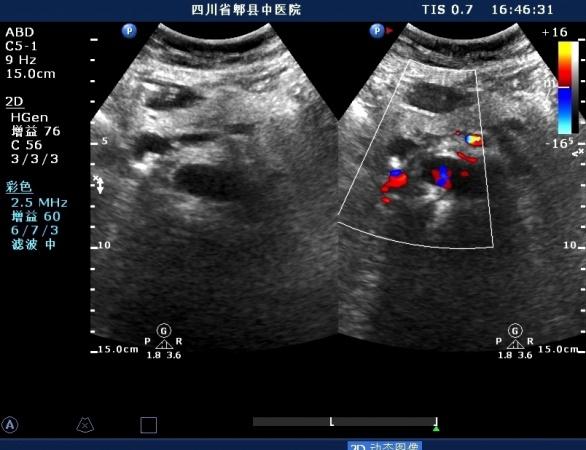

左肝内胆管结石